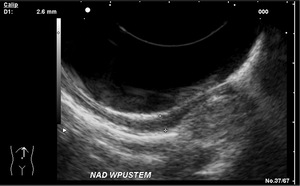

Podstawową metodą rozpoznawania raka połączenia przełykowo-żołądkowego jest badanie endoskopowe połączone z pobraniem wycinka do badania histopatologicznego. Staramy się ustalić umiejscowienie głównej masy guza w odniesieniu do wpustu żołądka. Zawsze należy obejrzeć okolicę wpustu w inwersji oraz ustalić, czy współistnieje przełyk Barretta. W celu określenia dokładnej topografii guza obraz endoskopowy porównujemy z obrazem radiograficznym. Endoultrasonografia jest badaniem najdokładniej oceniającym cechę T, czyli stopień zaawansowania pierwotnego ogniska nowotworu, co ma szczególne znaczenie w odróżnianiu raka wczesnego od zaawansowanego. Niezwykle istotne jest też ustalenie rzeczywistego zakresu zmian nowotworowych (ryc. 3).